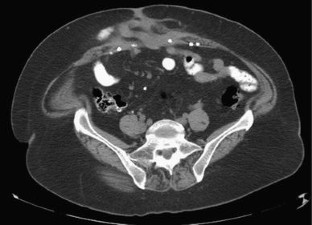

Mesh ingrowth with concomitant bacterial infection resulting in inability to explant: a failure of mesh salvage

Removal is the standard treatment for mesh infection following prosthetic hernia repair. However, certain types of mesh may be less amenable to removal even in the setting of active infection; we present four such cases, all involving the same composite mesh.

Four high-risk patients underwent Parietex mesh implantation for large ventral wall hernias and developed subsequent Staphylococcus infections with attempted explantation of infected mesh and wound care.

There was inability to completely explant mesh in all four cases, leading to chronic purulent wounds and long-term complications.

While mesh infection is a recognized complication of prosthetic hernia repair, many synthetic meshes form a slimy biofilm and thus can be removed relatively easily. However, the structural qualities of certain types of mesh create ingrowth into tissues even in the setting of infection, resulting in inability to explant with subsequent long-term chronic wound complications.